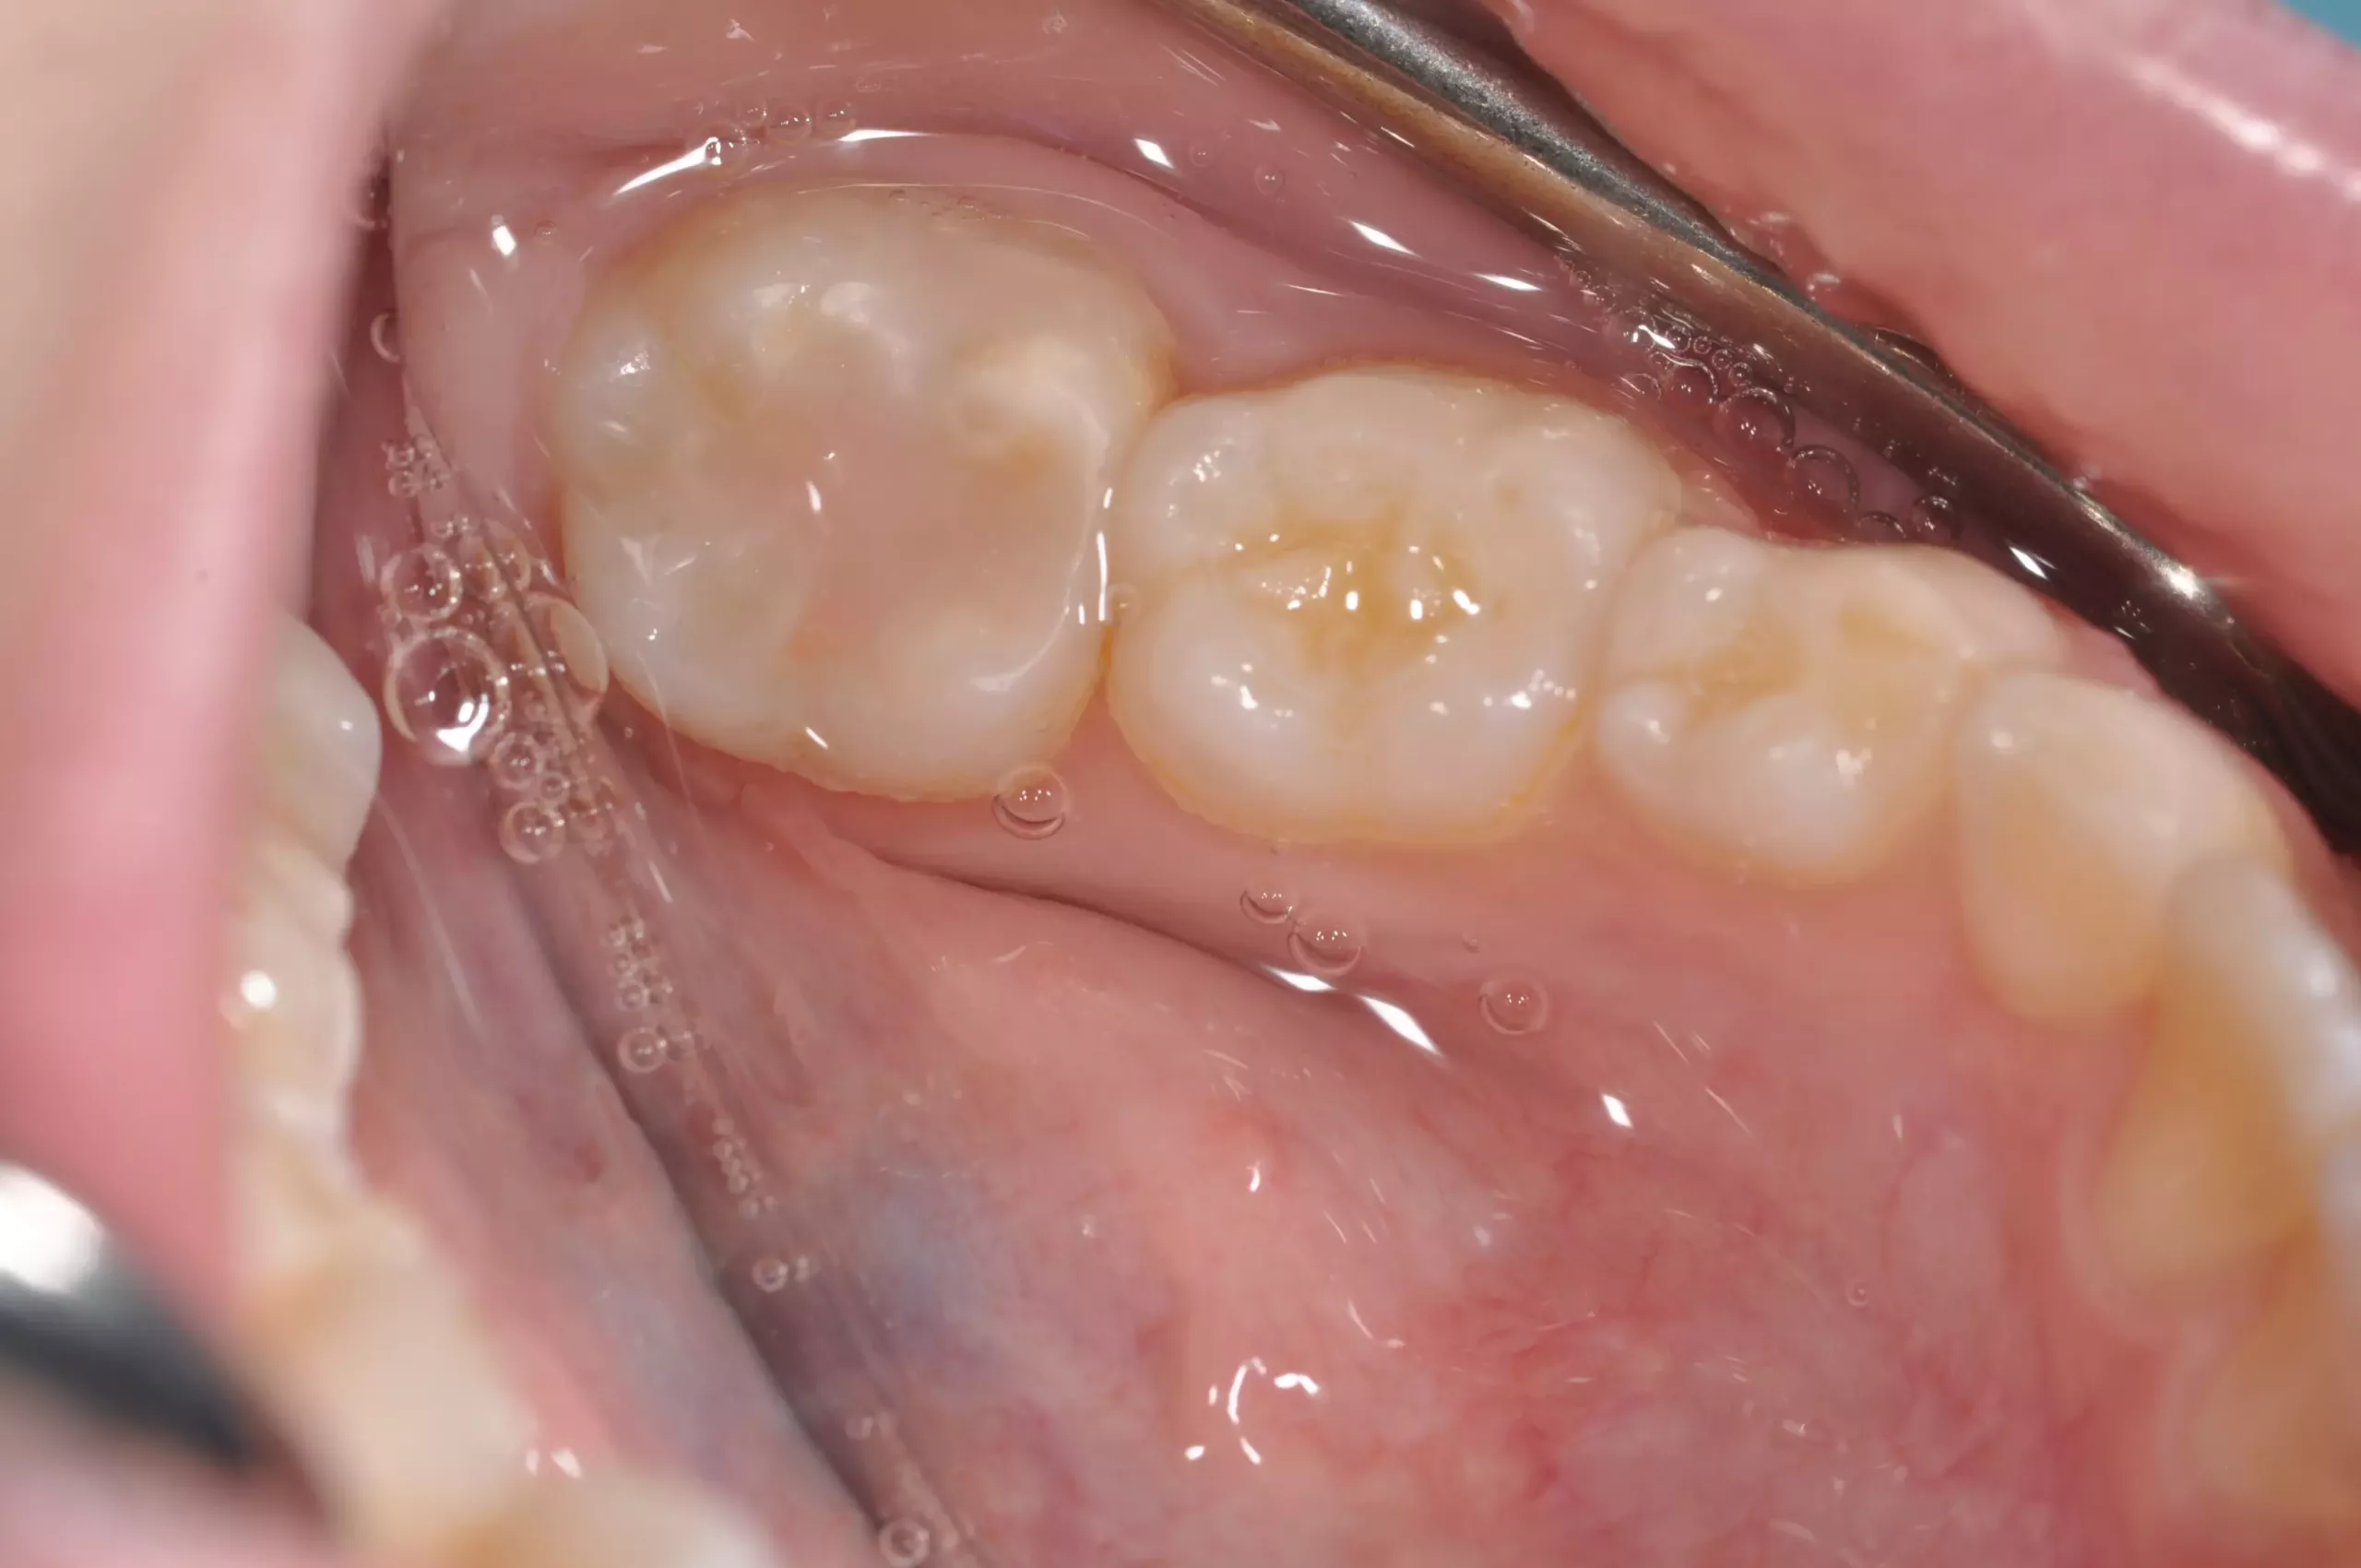

Typisch sind bei der leichten Form der Erkrankung weiße, cremige oder gelblich bis braune Opazitäten (Abb. 1). Im Gegensatz zur Dentalfluorose zeigt sich eine große Variabilität in Form, Farbe und Größe an den Zähnen innerhalb einer Mundhöhle. Bei der schweren Form bricht die Schmelzoberfläche nach dem Durchbruch des Zahnes im okklusalen Kontaktbereich aufgrund der Kaukräfte ein oder die Zähne weisen bereits im Durchbruch Defekte und Hypoplasien auf (Abb. 2).